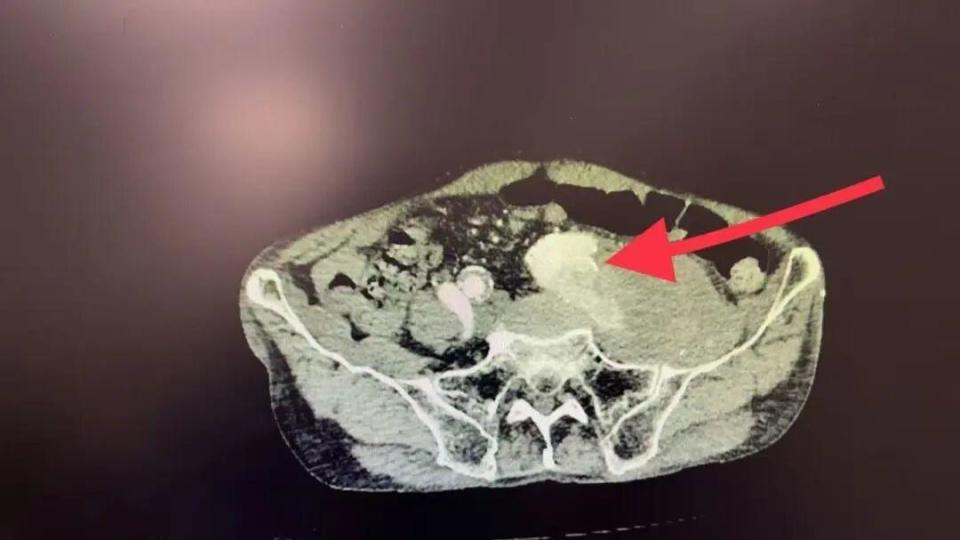

半岛网11月4日讯(记者 孙贴静 通讯员 刘裕) “左腿又肿又痛,连走路都成问题……”10天前,85岁的胡爷爷(化名)左腿突然肿胀疼痛,牵连着腹部隐隐发胀。在当地尝试土方子治疗后,症状反而加重。焦急的家人带他来到北京大学人民医院青岛医院血管外科,检查结果并非那么简单:髂动脉瘤破裂并假性动脉瘤形成,如同一颗“定时炸弹”藏在体内!

“患者入院时情况很严重,左侧髂动脉瘤已破裂出血,形成血肿压迫髂静脉,导致左腿严重肿胀。”血管外科医护团队回忆,破裂位置位于髂内动脉,且血管严重扭曲,如同被乱麻堵住的管道,让手术难度倍增。

专家介绍,手术第一大难点在于血管破裂后,内部结构混乱,真正的血管通道,也就是真腔,被压得像一条缝隙,而假腔和血肿空间很大,导丝稍有不慎就会走错路,一旦进入假腔操作,可能导致破裂加剧。手术团队凭借丰富的经验,成功将导丝精准送入了真腔。手术第二大难点在于破裂点位于髂内动脉的起始部,这是一个关键的血管岔路口。手术团队要用覆膜支架封住破口,但这个补丁会同时堵住髂内动脉的入口。为避免后续血流冲击导致新的问题,手术团队要先将这个分支血管安全地废弃掉。因此,团队先精确栓塞了左髂内动脉,再成功植入覆膜支架,完美覆盖了破裂点,恢复了主干血流的通畅。

术后复查显示:患者体内“炸弹”被成功拆除,血肿明显吸收,腿肿逐渐消退,患者已经顺利出院。